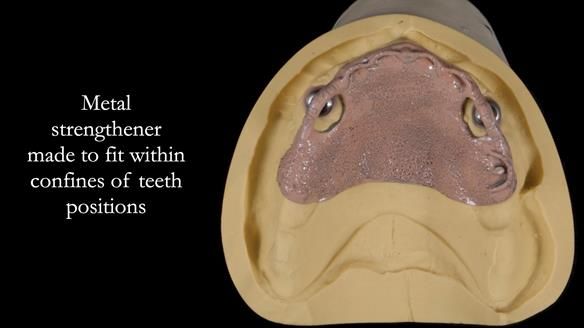

2. The upper denture, horseshoe-shaped and metal-reinforced, rocks on the ridge, causing wear on Locator abutments and a fractured upper right tooth.

The detailed clinical situation and treatment process are outlined below, with clinical work provided by me and technical work by Rowan Garstang. New complete implant supported complete dentures were made. The new upper denture had ‘almost’ full palatal extension for the non-splinted implants following ITI guidelines. A decision was reached to retain the worn Kerator attachments, as their removal could potentially accelerate implant failure. The treatment spanned five visits for denture fitting and one review. Alisdair expressed great satisfaction with the treatment, noting a significant enhancement in his overall quality of life.